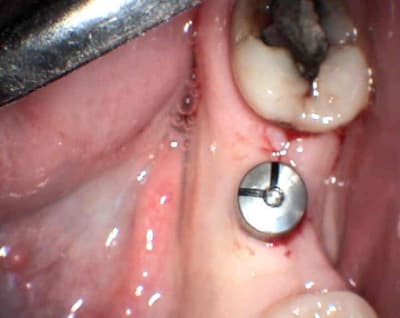

je relance le sujet

vu aujourd'hui patiente à qui j'ai posé il y à 5 semaines un axiom en 36 sans aucun soucis perop ni postop je la revois aujourd'hui elle présente un petit épulis crestal en regard de la tête de vis de cicat et petite perte crestale

je lui mets la vis haute demain pour dégager autour de la tête cette zone inflammatoire et ou infectieuse.

ce ne serait pas ta vis de couverture qui est mal vissée?

+1

or il me semble l'avoir bien bloqué et sur l'axiom la tête de vis dépasse comme ça , mais je pense à ça car je ne vois rien d'autre (en plus papulis crestal juste en regard ) c'est pour ça que je la revoie demain pour mettre la vis de cicatrisation à la place de la vis de couverture.

c'était pas par rapport à la radio que je disais ça, ça m'est déjà arrivé, faut faire gaffe à enlever tout le sang à l'intérieur de l'implant avant de visser.

ta remarque sur le sang est intéressante demain je te dirai ce que j'y ai vu après dépose de la vis de couv